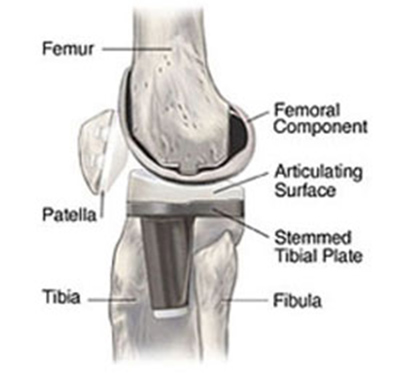

Cruciate retaining total knee arthroplasty (TKA)   Biomet Vanguard 360 Revision Knee System

Cruciate retaining TKA Cruciate retaining TKA Biomet Vanguard 360 knee revision Biomet Vanguard 360 knee revision

68 year-old woman treated for severe left knee osteoarthritis This replaced a loose prior total knee arthroplasty. The patellar button was left in place. A surgical drain is in place, and there is subcutaneous gas from the recent surgery.